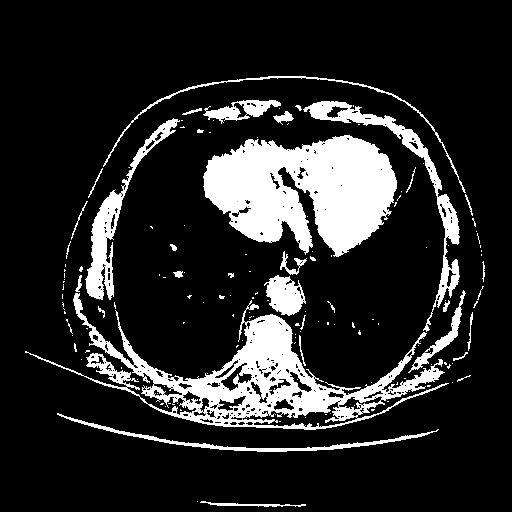

Slice 70 Targeting Evaluation

Patient ID: BC23122020

Model: cytran

Slice: Slice_70

Slice Thickness: 2.5mm

Conversion: NATIVE β VENOUS

4Γ3 grid: Rows show different image types (Original NATIVE, Reconstructed NATIVE, Original VENOUS, Generated VENOUS), Columns show windowing techniques (No Window, Lung Window, Mediastinum Window)